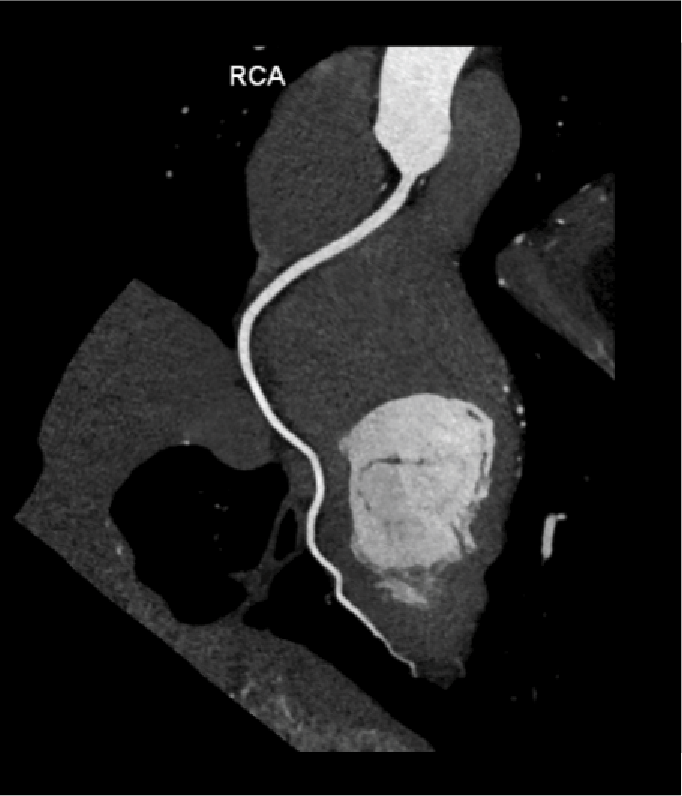

Tomografía cardiaca

Este estudio es adquirido con un tomógrafo de alta velocidad y baja radiación que permite evaluar las arterias coronarias y demostrar la ausencia o la presencia de placas ateromatosas, que son las que ocasionan un infarto (enfermedad arterial coronaria). Mediante la emisión de rayos X es posible obtener imágenes bidimensionales y tridimensionales del exterior y del interior de las arterias coronarias, del corazón y de la función cardiaca.

Cuando es necesario hacer una evaluación mas precisa de tus arterias coronarias la tomografía cardiaca permite, mediante la inyección de contraste por una vena del brazo, estudiar el interior de las arterias y demostrar si existen o no placas que impiden el paso de sangre hacia el corazón, a esta modalidad de la tomografía cardiaca le conocemos como angiotomografía coronaria, que se adquiere en 30 a 60 minutos, y es hoy día el estudio mas confiable para evaluar en forma no invasiva las arterias que nutren al corazón y que cuando se enferman pueden ocasionarte un infarto.

Existen otras indicaciones de la tomografía cardiaca que permiten evaluar las válvulas del corazón y de los grandes vasos como la aorta.